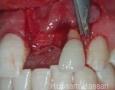

Pictures

Surgery